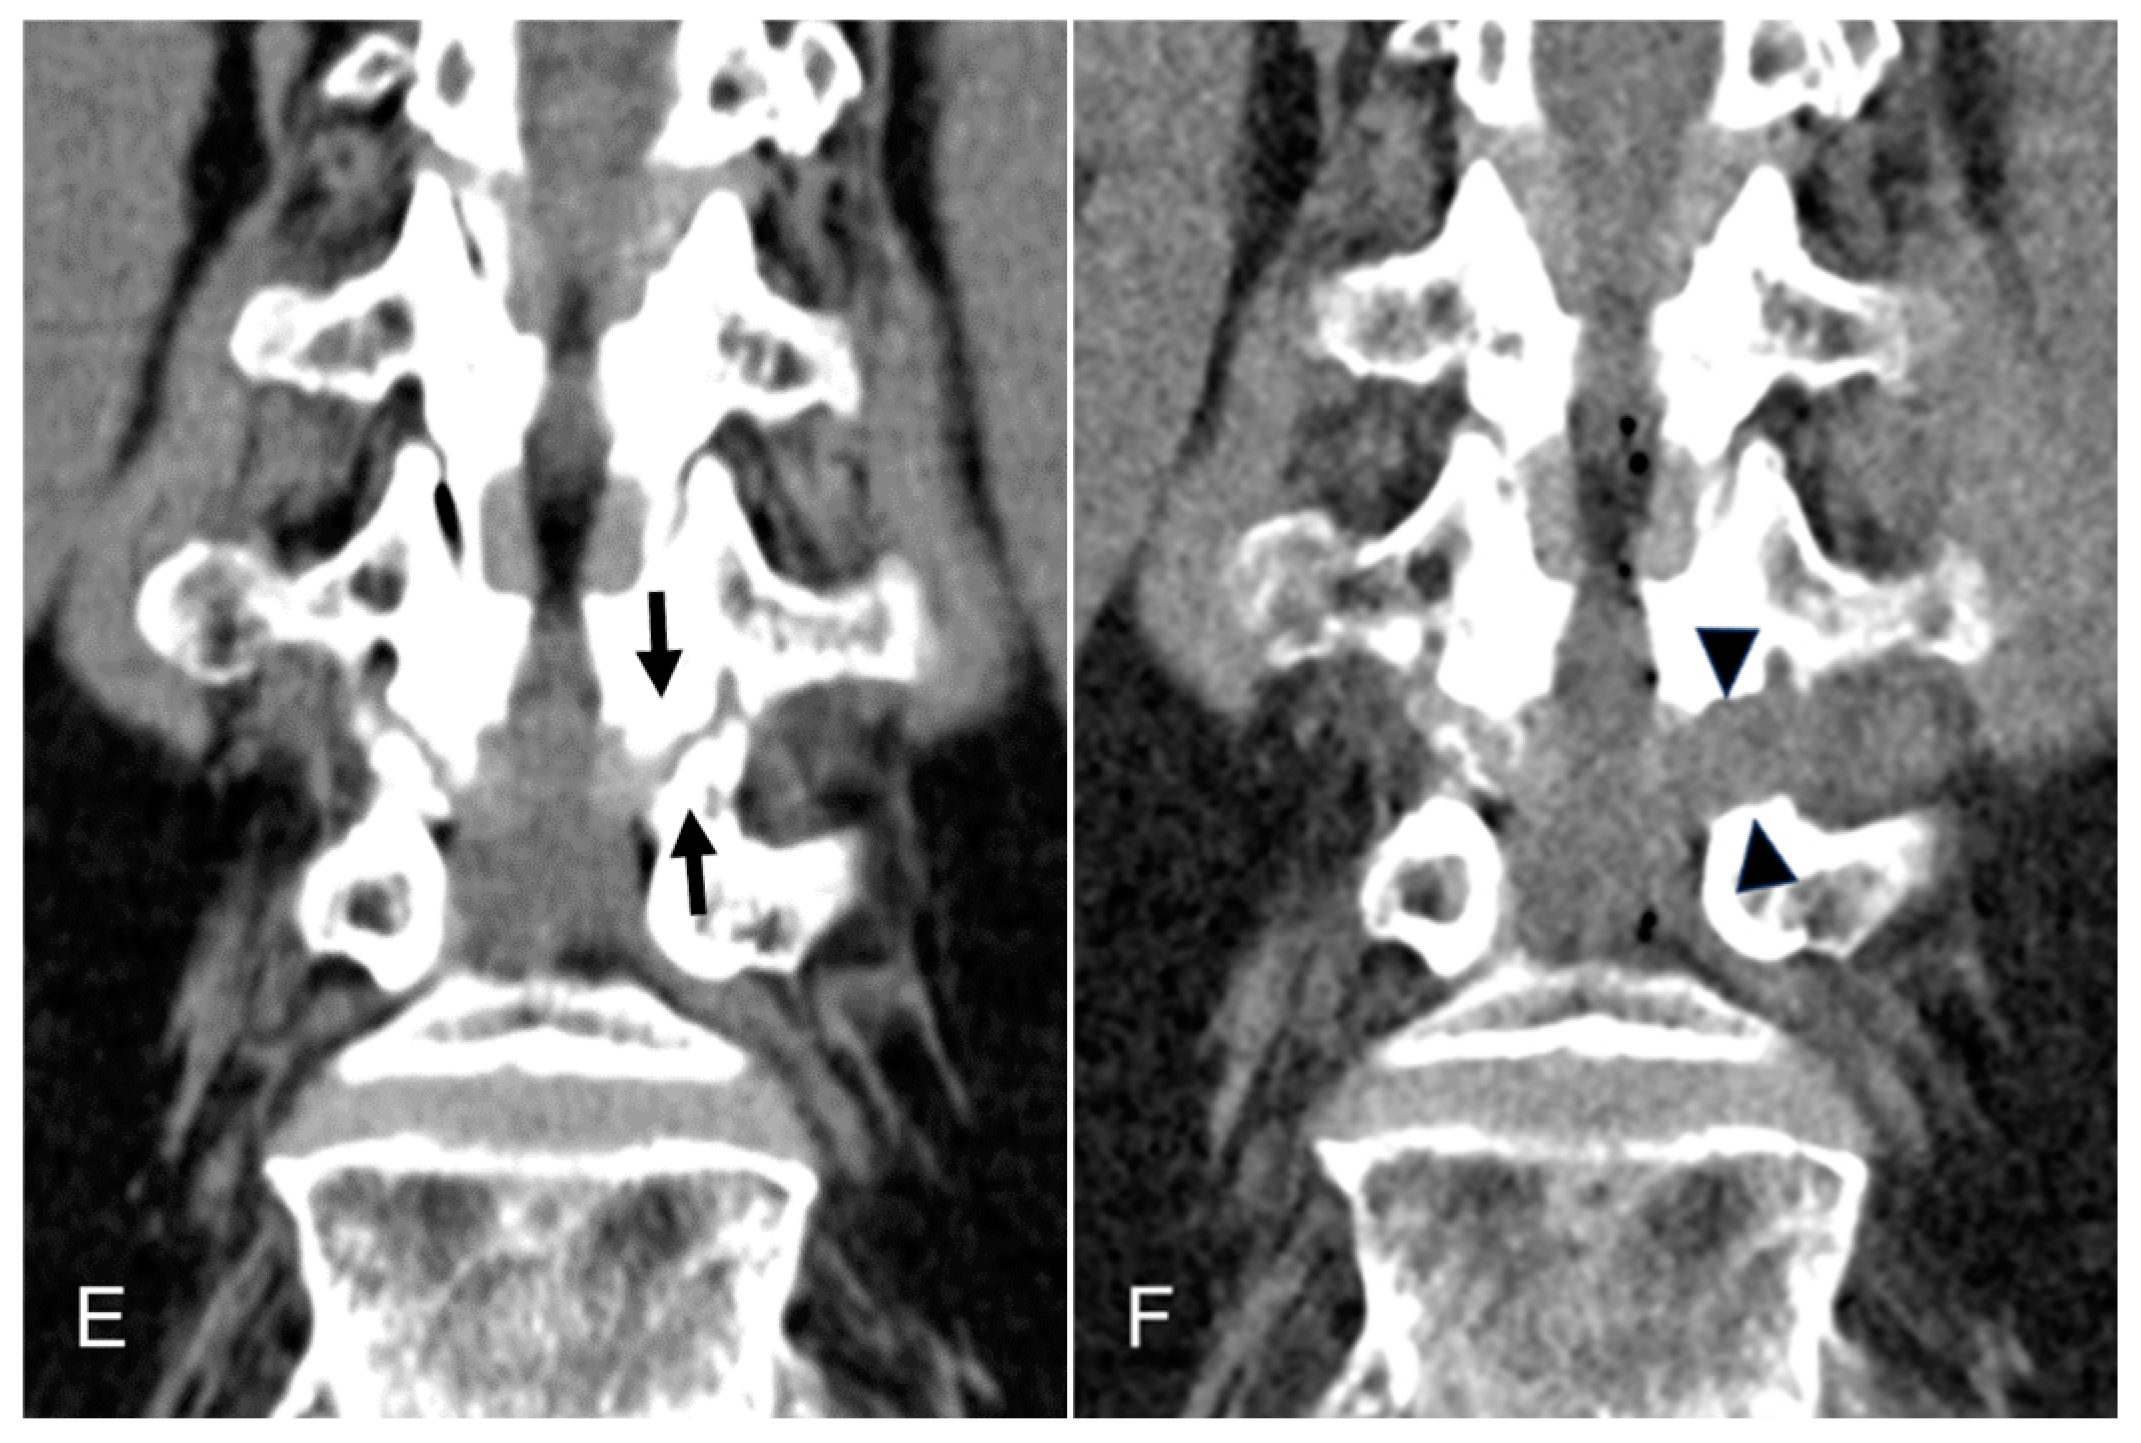

Figure 3. An illustrative case of an 81-year-old female patient treated with TELLRD. (a) Preoperative axial CT showing central and lateral recess stenosis at the L3-L4 level (arrows). (b) Postoperative axial CT showing lateral spinal canal decompression following undercutting of the hypertrophic SAP and LF compressing the TNR (arrowheads). (c) Preoperative sagittal CT showing lateral recess stenosis at the L3-L4 level (arrows). (d) Postoperative sagittal CT showing lateral spinal canal decompression following undercutting of the hypertrophic SAP and LF compressing the TNR (arrowheads). (e) Postoperative coronal CT showing lateral recess stenosis at the L3-L4 level (arrows). (f) Postoperative coronal CT showing lateral spinal canal decompression following undercutting the SAP and LF compressing the TNR (arrowheads). TELLRD, transforaminal endoscopic lumbar lateral recess decompression; SAP, superior articular process; LF, ligamentum flavum; TNR, traversing nerve root.